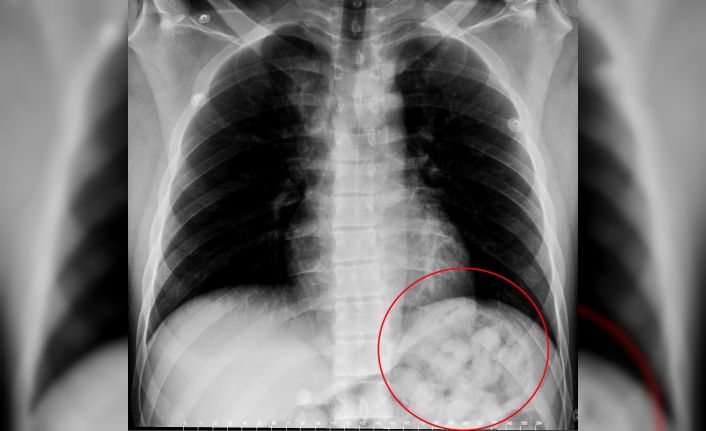

Edinilen bilgiye göre, 5 gün önce Van’dan otobüsle Ankara’ya gelen O. Zahed Ahmed Narziveh rahatsızlanınca hastaneye kaldırıldı. Ankara Şehir Hastanesine getirilen şahsın röntgen görüntüleri gerçeği ortaya çıkardı. Şahsın midesinde 890 gram ağırlığında 2’si patlamış halde 72 kapsül olduğu ve kapsüllerin patlaması ile fenalaştığı belirlendi. Mahkeme kararına istinaden ameliyata alınarak midesindeki metamfetamin kapsülleri çıkartılan zanlı, Ankara Emniyet Müdürlüğüne bağlı Narkotik Suçlarla Mücadele ekiplerince hastanedeki 5 günlük tedavisinin ardından adliyeye sevk edildi.Karnından uyuşturucu zulası çıktı

Van’dan otobüsle Ankara’ya gelen yabancı uyruklu şahıs, yuttuğu 72 kapsül metamfetamin kapsülünün midesinde patlaması üzerine rahatsızlanarak hastaneye kaldırıldı.